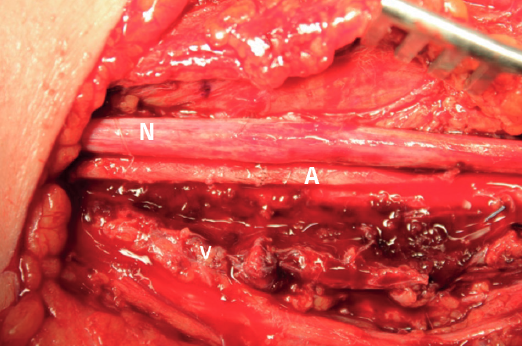

En el quirófano, se realiza incisión en la cara medial del brazo y, tras una disección cuidadosa, se localiza el paquete neurovascular formado por la arteria braquial, el nervio mediano y la vena basílica (Figura 3). Destaca la presencia de un gran hematoma que se reseca, así como el cuerpo extraño causante de la lesión.

Figura 3. Disección del paquete neurovascular. A: arteria braquial; N: nervio mediano; V: vena basílica. En la imagen de debajo se observa el aspecto hemorrágico del nervio mediano.